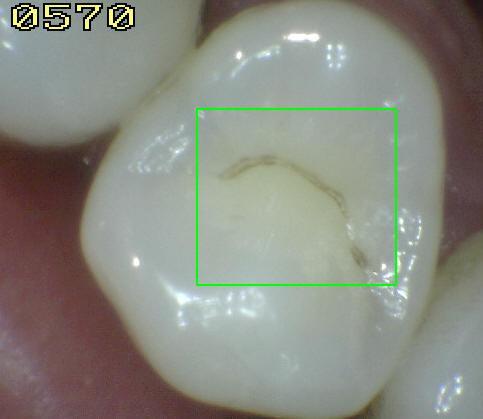

2. Icdas 4

1. HALLAZGO CLÍNICO: sombra oscura subyacente a dentina

1. caries No cavitacional con sombra visible de color gris o azul que compromete dentina.

1. ACTIVIDAD: Es útil determinar el tiempo de estancamiento de la placa en el sitio de inspección (Placa de más de 72 horas); para esto solemos utilizar el Índice de placa oclusal, Un valor =>2 nos determina una lesión activa